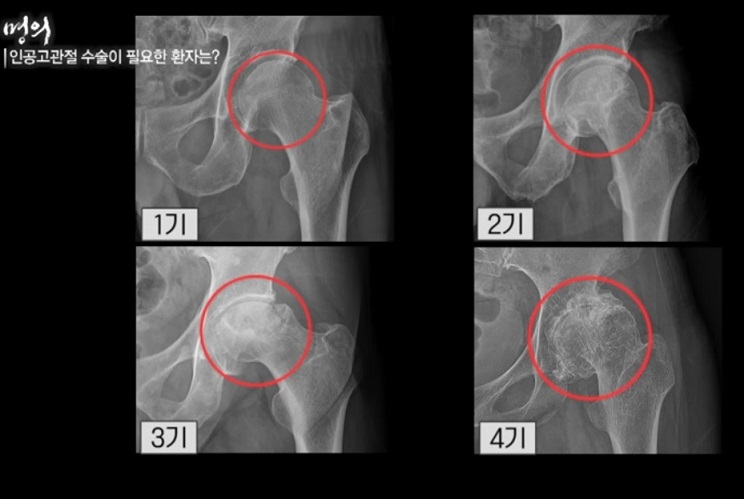

- 인공 고관절 수술이 필요한 환자는?

인공고관절 수술, 언제 해야 할까?

그렇다면 젊은 환자들은 언제 인공 고관절 수술을 받아야 할까?

또 고령 환자가 늘고 있는 상황에서 몇 살까지 수술이 가능할까? 인공고관절 수술의 적기와 수술 후 관리법에 대해 명의에서 공개한다.